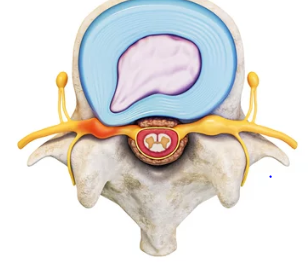

허리디스크는 많은 현대인들이 겪고 있는 흔한 질환 중 하나입니다. 이는 척추 뼈 사이에 위치한 디스크가 손상되어 신경을 압박하게 되면서 발생하는 통증과 다양한 증상을 유발합니다. 전조증상으로는 허리의 불편함과 통증이 점차적으로 시작되며, 이는 다리까지 방사되는 경우도 있습니다. 조기 발견과 적절한 치료가 중요한데, 이는 증상의 악화를 막고, 더 나은 삶의 질을 유지할 수 있게 도와줍니다. 비수술적 치료방법부터 수술적 치료까지 다양한 옵션이 있으며, 환자의 상태와 증상에 따라 최적의 치료 계획을 세울 수 있습니다. 이 글에서는 허리디스크의 전조증상을 인지하는 방법과, 효과적인 치료 방안에 대해 자세히 알아보겠습니다. 오늘은 허리 디스크 전조증상 및 치료방법에 대해 알아보겠습니다.

허리디스크는 많은 현대인들이 겪고 있는 질환 중 하나로, 척추의 디스크가 탈출하거나 손상되어 신경을 압박함으로써 발생하는 통증 및 기타 증상을 일으키는 상태를 말합니다. 이 질환은 잘못된 자세, 과도한 체중, 또는 반복적인 스트레스 등 다양한 원인에 의해 발생할 수 있으며, 특히 장시간 앉아 있는 생활습관이 있는 사람들에게서 자주 발견됩니다. 전조증상으로는 허리 통증, 다리 저림, 감각 이상 등이 있으며, 이러한 증상들은 일상생활에 큰 불편을 초래할 수 있습니다. 치료 방법은 증상의 정도와 개인의 상태에 따라 다르지만, 일반적으로는 물리치료, 약물치료, 그리고 필요한 경우 수술적 치료가 고려될 수 있습니다. 조기 진단과 적절한 치료 계획을 통해 허리디스크로 인한 통증과 불편을 줄이고, 건강한 척추 상태를 유지할 수 있습니다.

허리 디스크, 또는 추간판 탈출증은 많은 사람들이 겪는 통증의 원인 중 하나입니다. 이 상태는 척추 사이에 위치한 디스크가 손상되거나 변형되어 신경을 압박할 때 발생합니다. 허리 디스크의 원인은 다양하지만, 가장 흔한 원인은 다음과 같습니다.